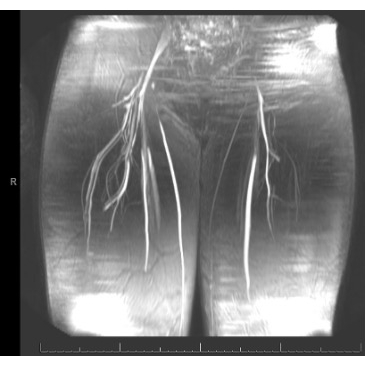

The athlete completed physical therapy with quick resolution of symptoms. He never required FFP. He played in his first game of the season 2 weeks after his formal diagnosis of Factor XI deficiency. One month later, a right lower extremity MR angiogram showed no structural vascular abnormality and a resolution of the hematoma with residual fascial thickening/inflammation.

Case Photo #2